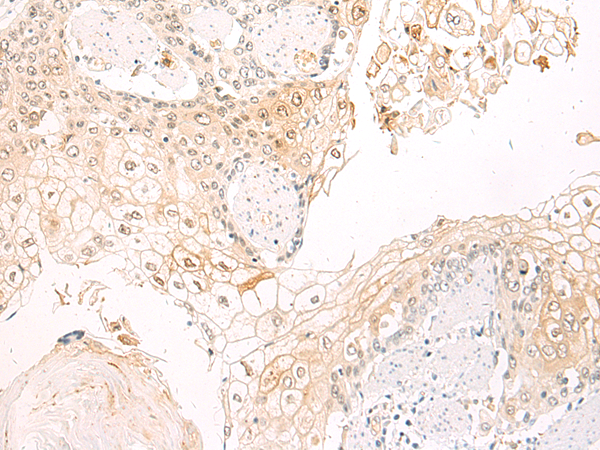

This gene encodes the integrin alpha M chain. Integrins are heterodimeric integral membrane proteins composed of an alpha chain and a beta chain. This I-domain containing alpha integrin combines with the beta 2 chain (ITGB2) to form a leukocyte-specific integrin referred to as macrophage receptor 1 ('Mac-1'), or inactivated-C3b (iC3b) receptor 3 ('CR3'). The alpha M beta 2 integrin is important in the adherence of neutrophils and monocytes to stimulated endothelium, and also in the phagocytosis of complement coated particles. Multiple transcript variants encoding different isoforms have been found for this gene. |

ELISA, IHC |

IHC positive control: |

Human esophagus cancer |

IHC Recommend dilution: |

50-100 |